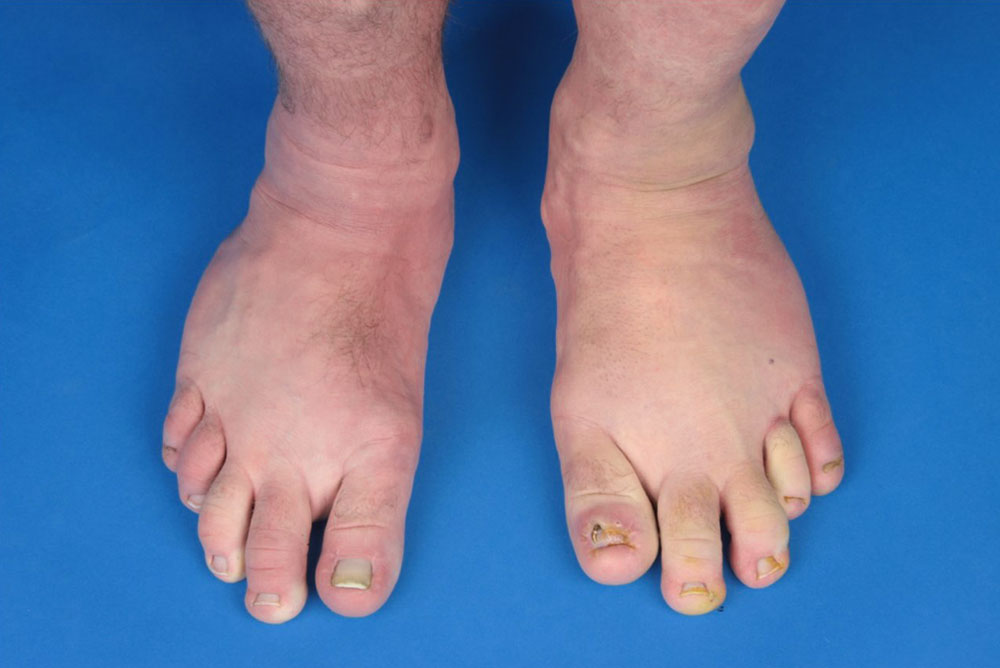

Der regionale Überwuchs mit vorherrschender Weichteilkomponente ist bereits bei Geburt vorhanden und betrifft am häufigsten die Füße. Der „CLOVE-Fuß“ hat ein charakteristisches Aussehen: Verbreiterung insbesondere des Vorfußes („ballonierte Hyperplasie“), fibroadipöse Weichteilvermehrung, Sandalenlücke.

Einzelne oder mehrere Zehen können vom Überwuchs betroffen sein. Im Gegensatz zum Proteus-Syndrom bleibt trotz des oftmals massiven Überwuchses einzelner Knochen deren Form weitgehend erhalten. Desweiteren finden sich Lipomatosen, mitunter großflächig, besonders am Rumpf. Häufig weisen Patienten mit CLOVES-Syndrom auch Lipoatrophien auf, diese betreffen meist die Arme. Der zugrundeliegende Mechanismus der Fettgewebsdysregulation ist bisher nicht verstanden.